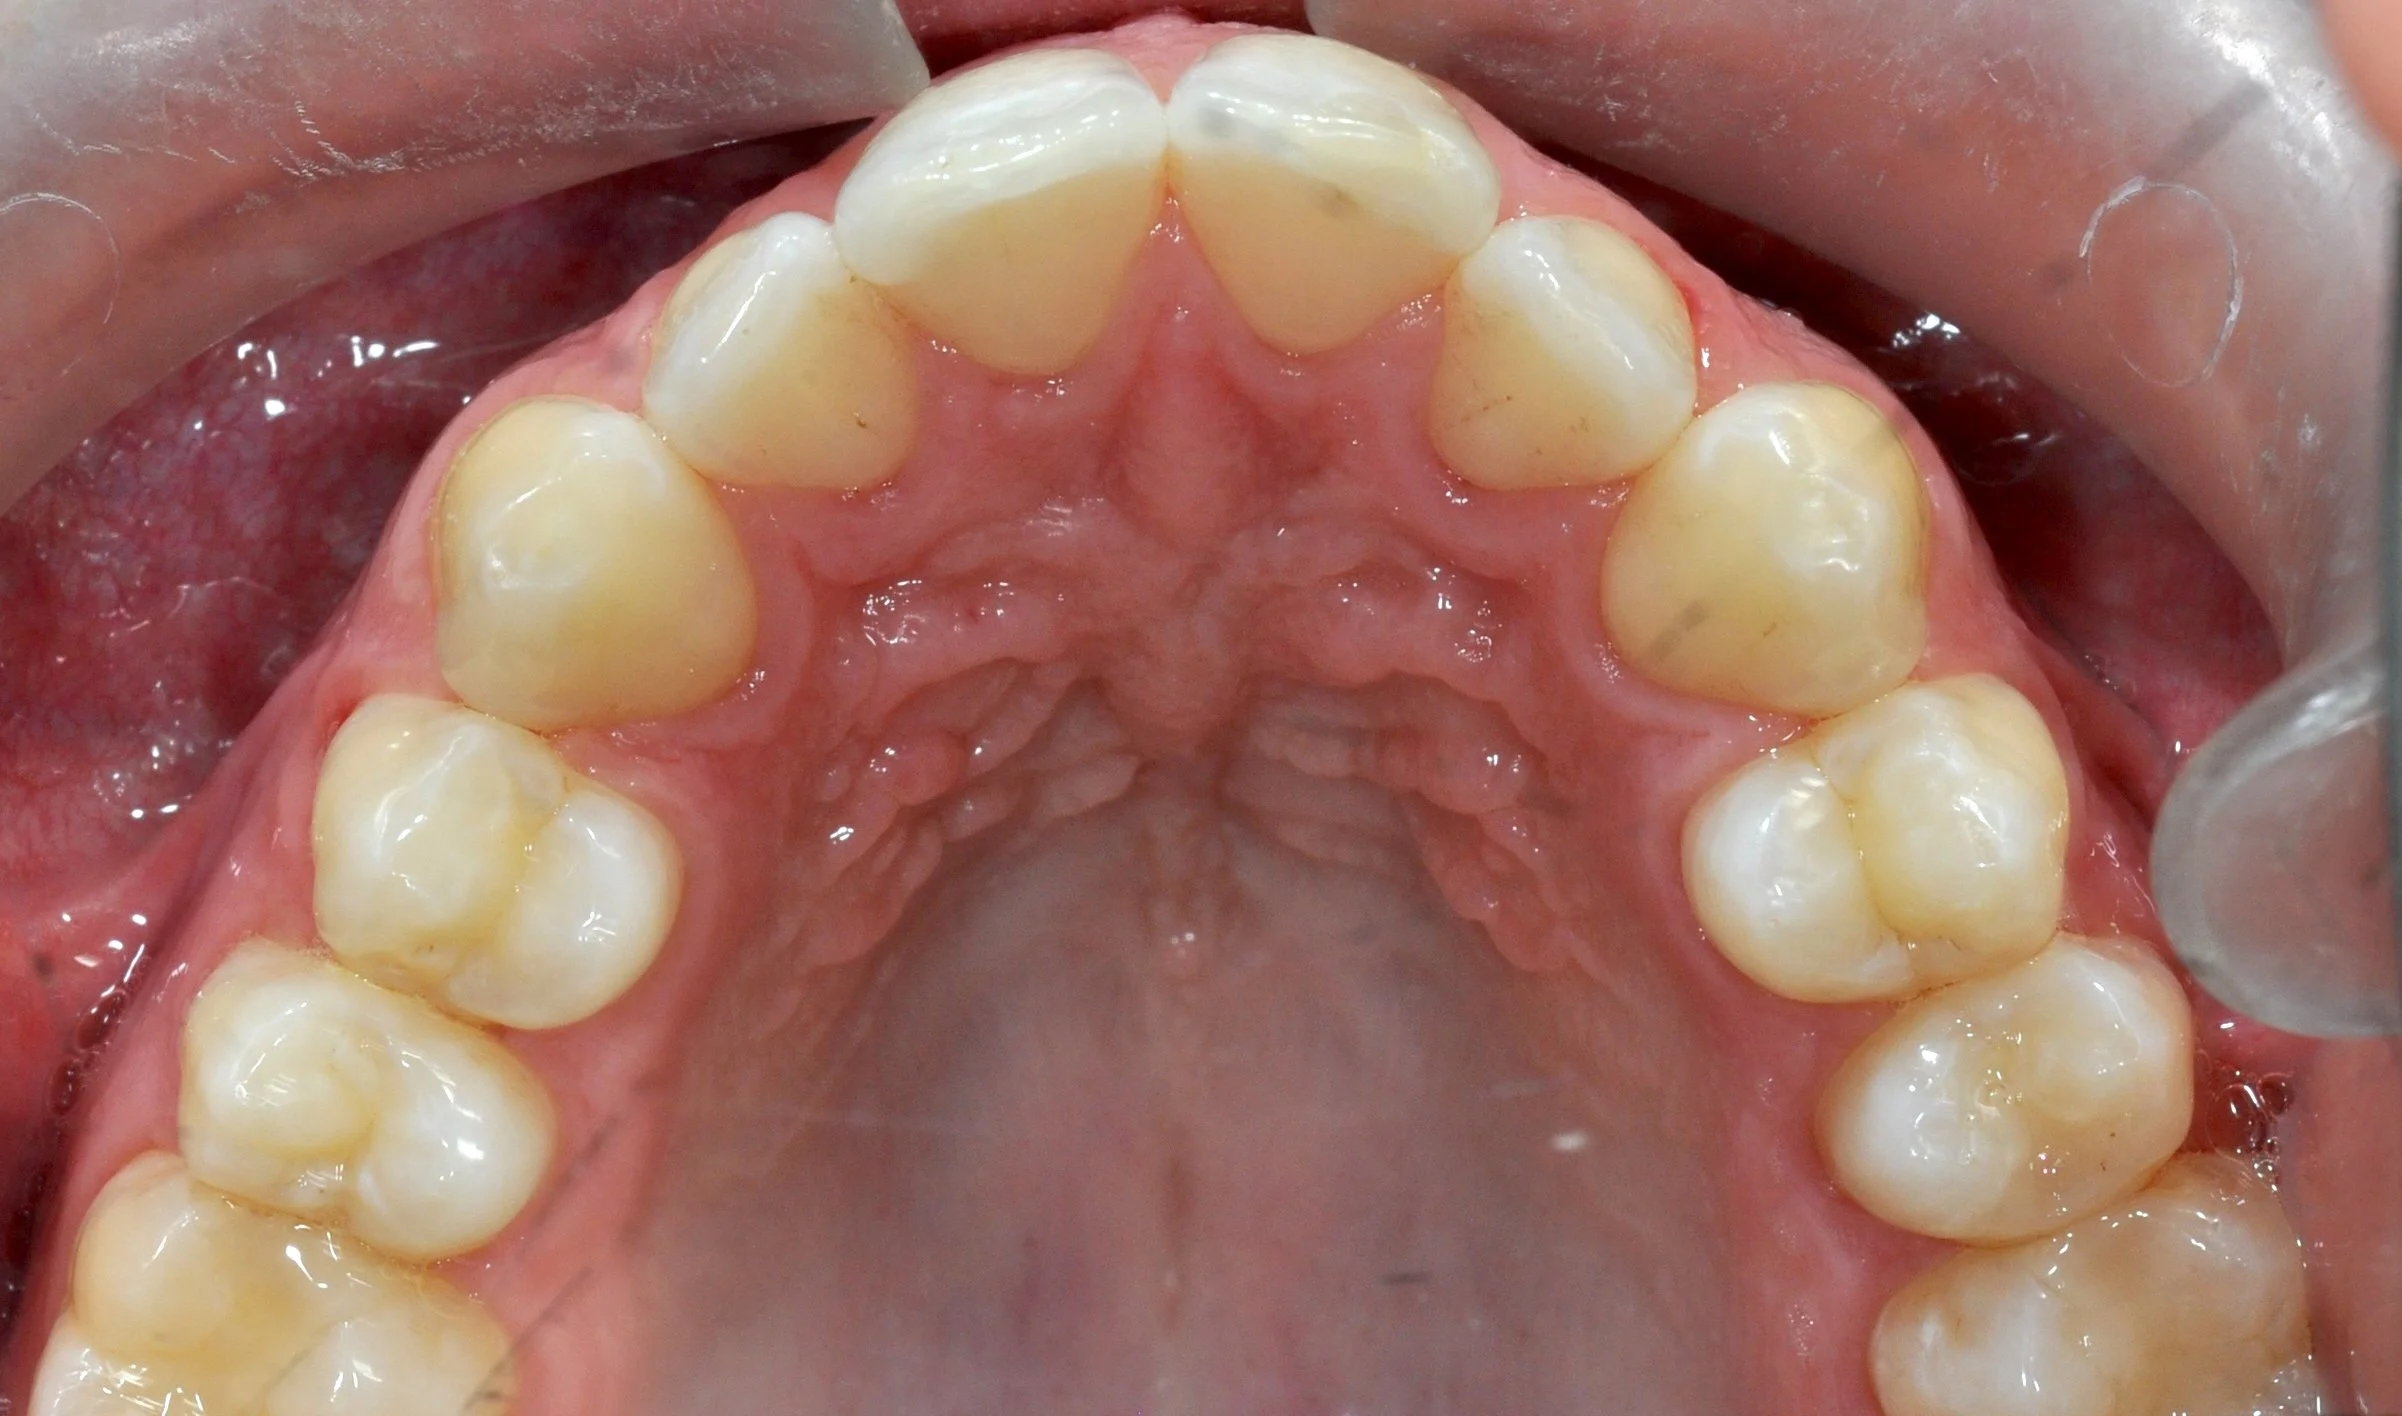

Caso 1 – Allineatori trasparenti in età evolutiva

Giovane paziente in fase di crescita con denti superiori troppo in avanti rispetto agli inferiori, arcate strette e rotazioni importanti di alcuni elementi.

PRIMA